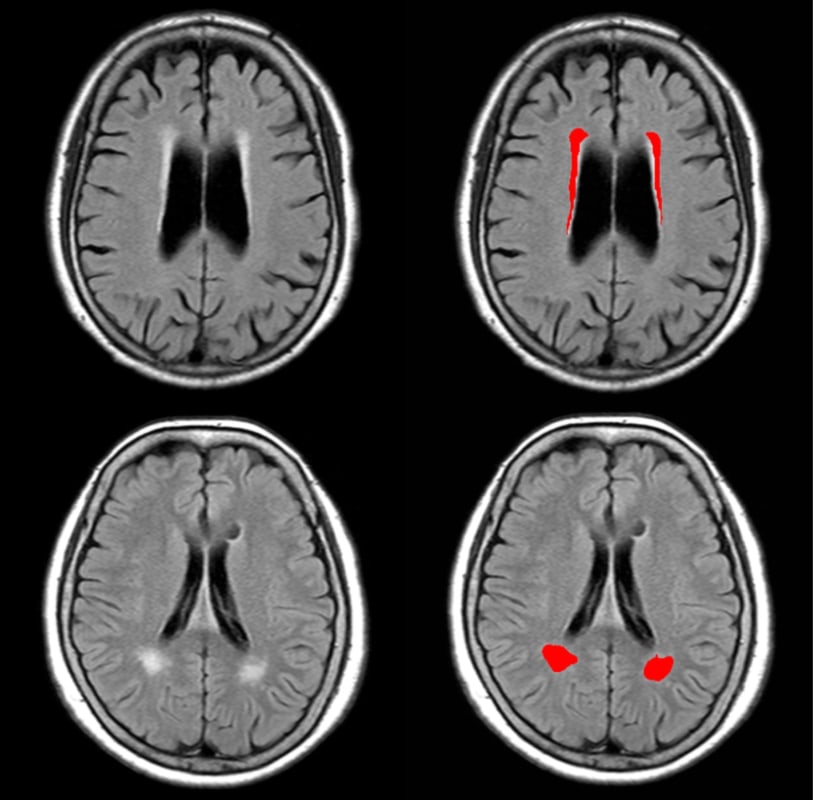

EIRL Brain Metry can provide consistent, automatic measurements for parameters that are subject to quantitative evaluation or variability among doctors, including the Evans index, Callosal angle, and white matter hyperintensities.